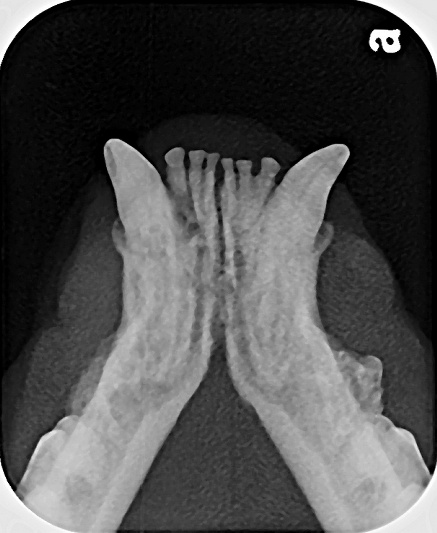

Example of a size 2 oral radiograph for the rostral mandible in a feline cadaver showing tooth resorption for the mandibular canines and third premolars